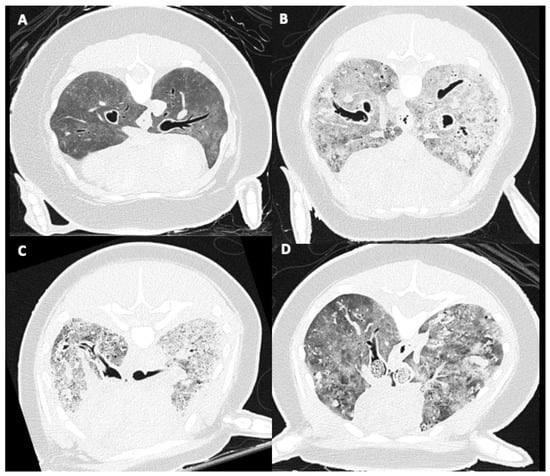

3.3. Tracheobronchial Changes

3.4. Pulmonary Parenchymal Attenuation Changes